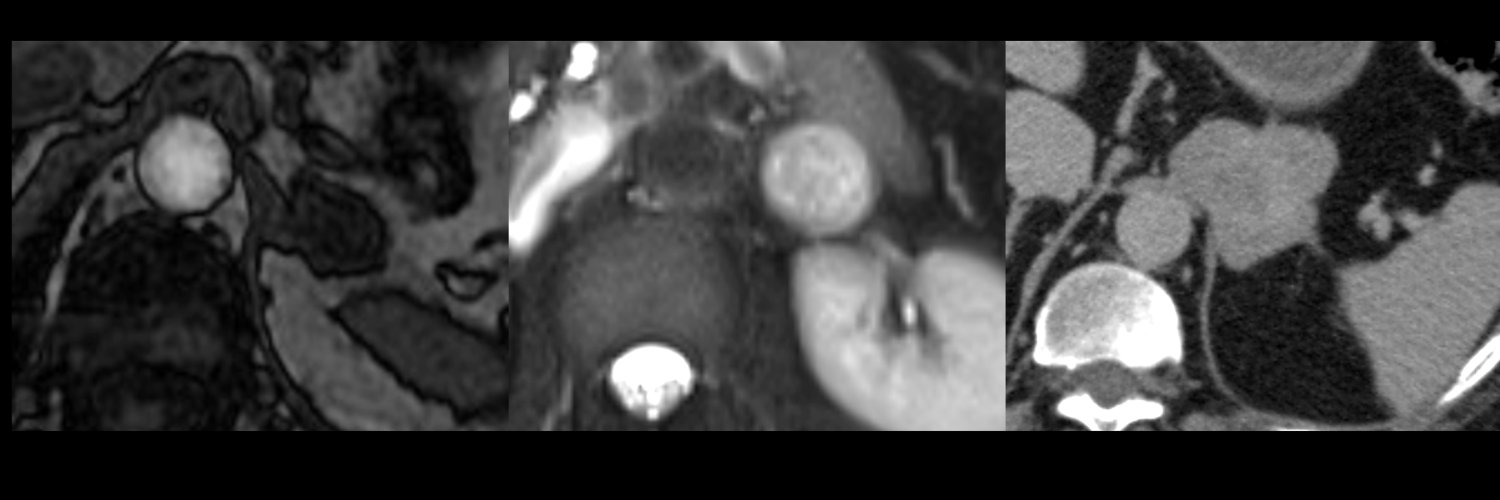

Check out this case & drop your answers in the comments below! Answer coming Friday! #SARgettable #SAR #Radiology